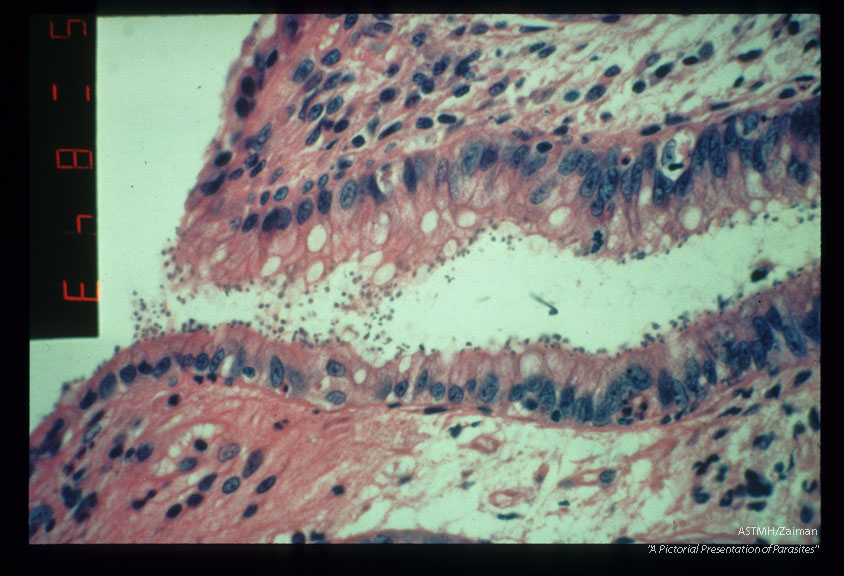

Photomicrographs showing parasites in rectum. H&E stain.

Cryptosporidium

Description: Photomicrographs showing parasites in rectum. H&E stain.